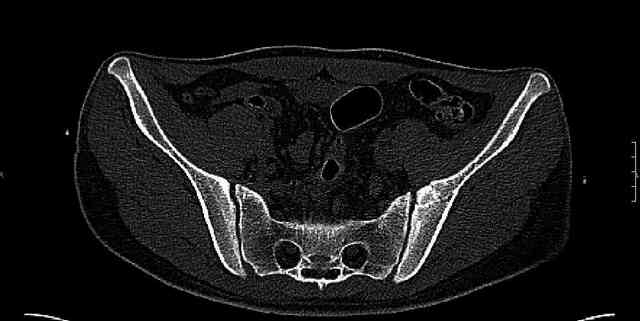

Some more images. Does it help to guess which part of the acetabulum is displaced?

Normal appearing SI joints and a healed posterior column limb... my bet's on caudal segment displacement.

While not claiming to have the best 3D brain around, it appears to me from the limited images available, that the caudal segment is stable from the symphysis to the SI joint on the fracture side. I would love to see the rest of the transverse CT images to see where the fracture line actually exits posteriorly on both the inner and outer tables of the ilium. In my hands,

assuming that the femoral head has followed the cephalad (dome) fragment, I would use an ilioinguinal approach and take down the fracture line from anterior to posterior, distracting with a lamina spreader, if necessary, to clean out and inspect the joint. I would then reduce the cephalad fragment to the caudal fragment using jungbluth or farabeuf clamp and screws and then apply a plate and screws. If the fracture exits posteriorly would you then favor an additional posterior approach to clean out and reduce from that side?